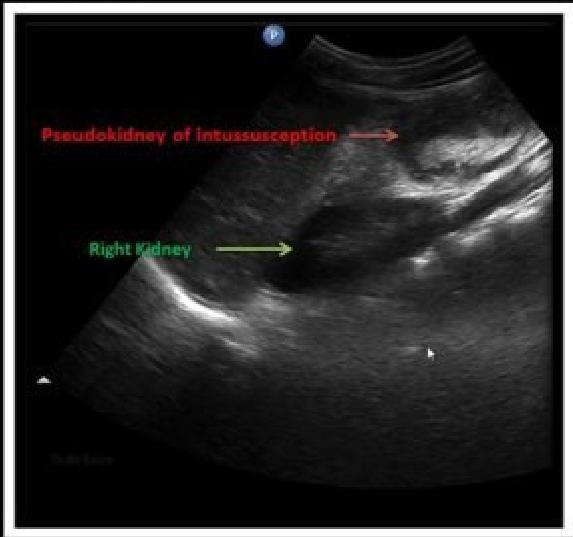

- Ultrasound is the method of choice and diagnostic â target sign.

- â Pseudkidney sign

Abdominal ultrasound (best initial test): often sufficient to confirm diagnosis Â

- Pseudokidney sign: This âpseudokidneyâ is made up of longitudinal layers of bowel wall.